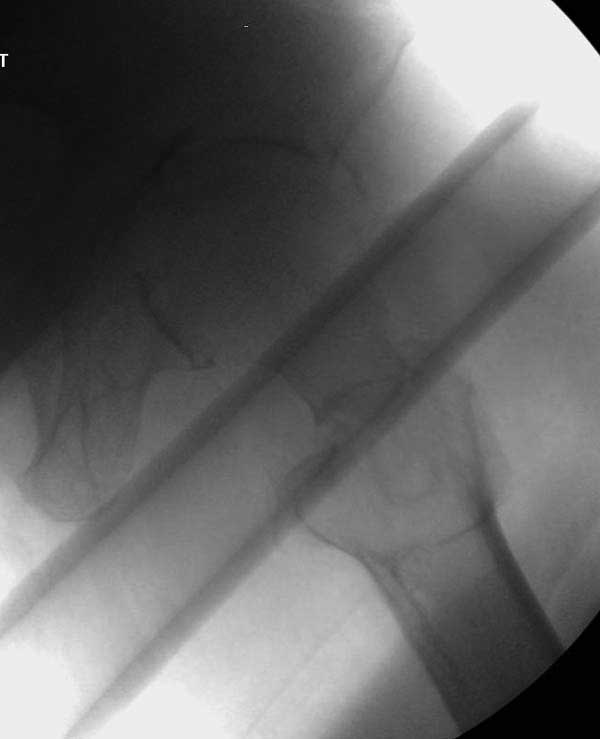

Первые снимки показывают технические погрешности установки DHS. Не была достигнута репозиция, конечность в флексии и шейка в ротации. Сегодня все меньше обращают внимание на параметры для оценки репозиции (S контуры Lowell в обеих проекциях и Garden Alignment Index, в норме 155 и 180 градусов), хотя такие простые тесты помогли бы дорепонировать смещение. Винт находится сзади в головке, что при нагрузке поменяет вектор и вместо компрессии в линии перелома срежет головку-Cut Out!

В зависимости от дистанции линии перелома и латерального кортекса надо использовать разной длины barrel, т.е. конец баррели не должен доходить до пределов перелома. Здесь конец длинного ствола упирается в медиальный фрагмент, что мешает созданию компрессии, а более короткий barrel создал бы запас для компрессии. В боковой пластине вместо 4х можно было ограничится двумя шурупами, потому что головка шурупа в 4.5 мм выдерживает давление до 350 кг.